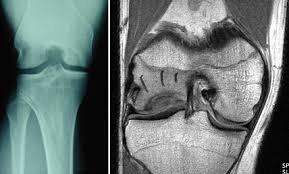

Osteochondritis dissecans (OCD) is a joint condition that occurs when a piece of bone and its overlying cartilage become loose due to a lack of blood supply. This can lead to pain, swelling, and potential joint instability, particularly in the knee. OCD commonly affects adolescents and young adults, often as a result of repetitive stress or minor trauma to the joint. Understanding the causes, symptoms, and treatment options for OCD is essential for managing the condition and preserving joint health.

OCD is a condition in which a portion of the bone beneath the cartilage in a joint loses its blood supply, leading to the separation of bone and cartilage. In some cases, the loose fragment may remain attached, while in others, it can break free and move within the joint, causing mechanical symptoms. OCD most commonly affects the knee, particularly the femoral condyles (the rounded ends of the thighbone), but it can also occur in other joints such as the elbow and ankle.